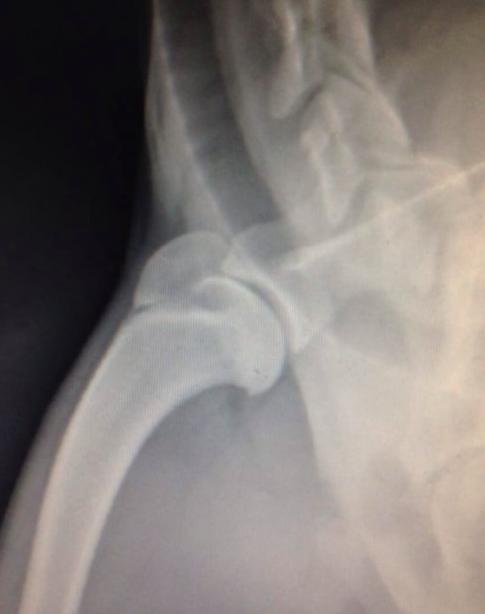

为了达到准确的评估结果,兽医会请放射科医生为小狗每个患病的部位进行X光片,可清楚了解到疾病的严重程度,而X光片是诊断这类疾病的最常用方式。

一般X光片能够满足诊断需求,但有一种更为精细的仪器叫关节镜检查,可在关节内放置一个小型摄像头,借助它可以直接观察小狗关节腔内的滑膜、软骨、半月板与韧带。

膝关节骨软骨病